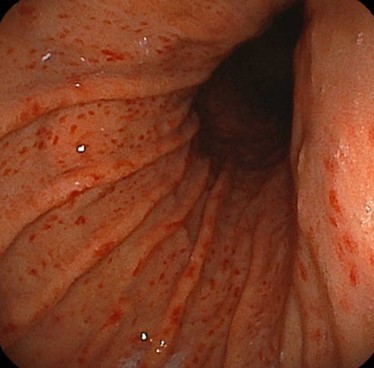

通常の色調(白色光)による観察

当院では内視鏡によるピロリ感染診断に加えて

胃がんや潰瘍などの有無も同時に診断します